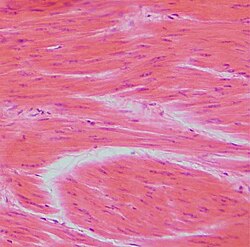

Glatki mišić (lat. textus muscularis nonstriatus) je uz poprečno-prugasti (skeletni) i srčani mišić jedna od 3 glavne vrste mišićnog tkiva. Glatki mišići su za razliku od skeletnih građeni od mnogo manjih vlakana promjera 1 do 5 µm, a duga su 20 do 500 µm. Nalaze se u građi krvnih i limfnih žila, crijeva, dušnika, mokraćnog mjehura , maternice, kože, unutrašnjih mišića oka itd. Glatko mišićno tkivo je specijalizirano za slabe i spore kontrakcije, a inervirano je od strane autonomnog živčanog sustava što znači da ne radi pod utjecajem volje. Za razliku od skeletnog mišićja, ti su mišići sposobni za dugotrajne kontrakcije i vrlo se teško zamaraju.

Glatki mišići nemaju tropomiozinski kompleks i nemaju pravilan raspored kao skeletni mišići. Građeni su od aktinskih i miozinskih niti. Aktinske niti su pričvršćene za gusta tjelešca koja mogu biti vezana za membranu ili razbacana po stanici. Između aktinskih niti se nalaze miozinske kojih ima 5-10 puta manje nego aktinskih koje se zrakasto šire prema sredini i sa svojim krajevima dodiruju miozinske niti koje ih povlače u suprotni smjer. Gusta tjelešca zapravo imaju jednaku ulogu kao i Z-membrane skeletnih mišića.